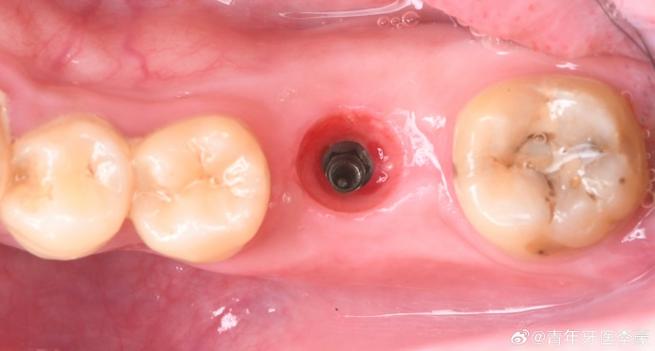

种植体植入位置或角度偏差:

(图片来源网络,侵删)- 位置不佳: 种植体植入时没有完全处于理想位置(如偏向唇颊侧或舌腭侧),导致最终牙冠无法与邻牙紧密贴合,形成缝隙。

- 角度偏差: 种植体长轴方向与理想位置有偏差,使得牙冠的邻面无法正确接触邻牙。